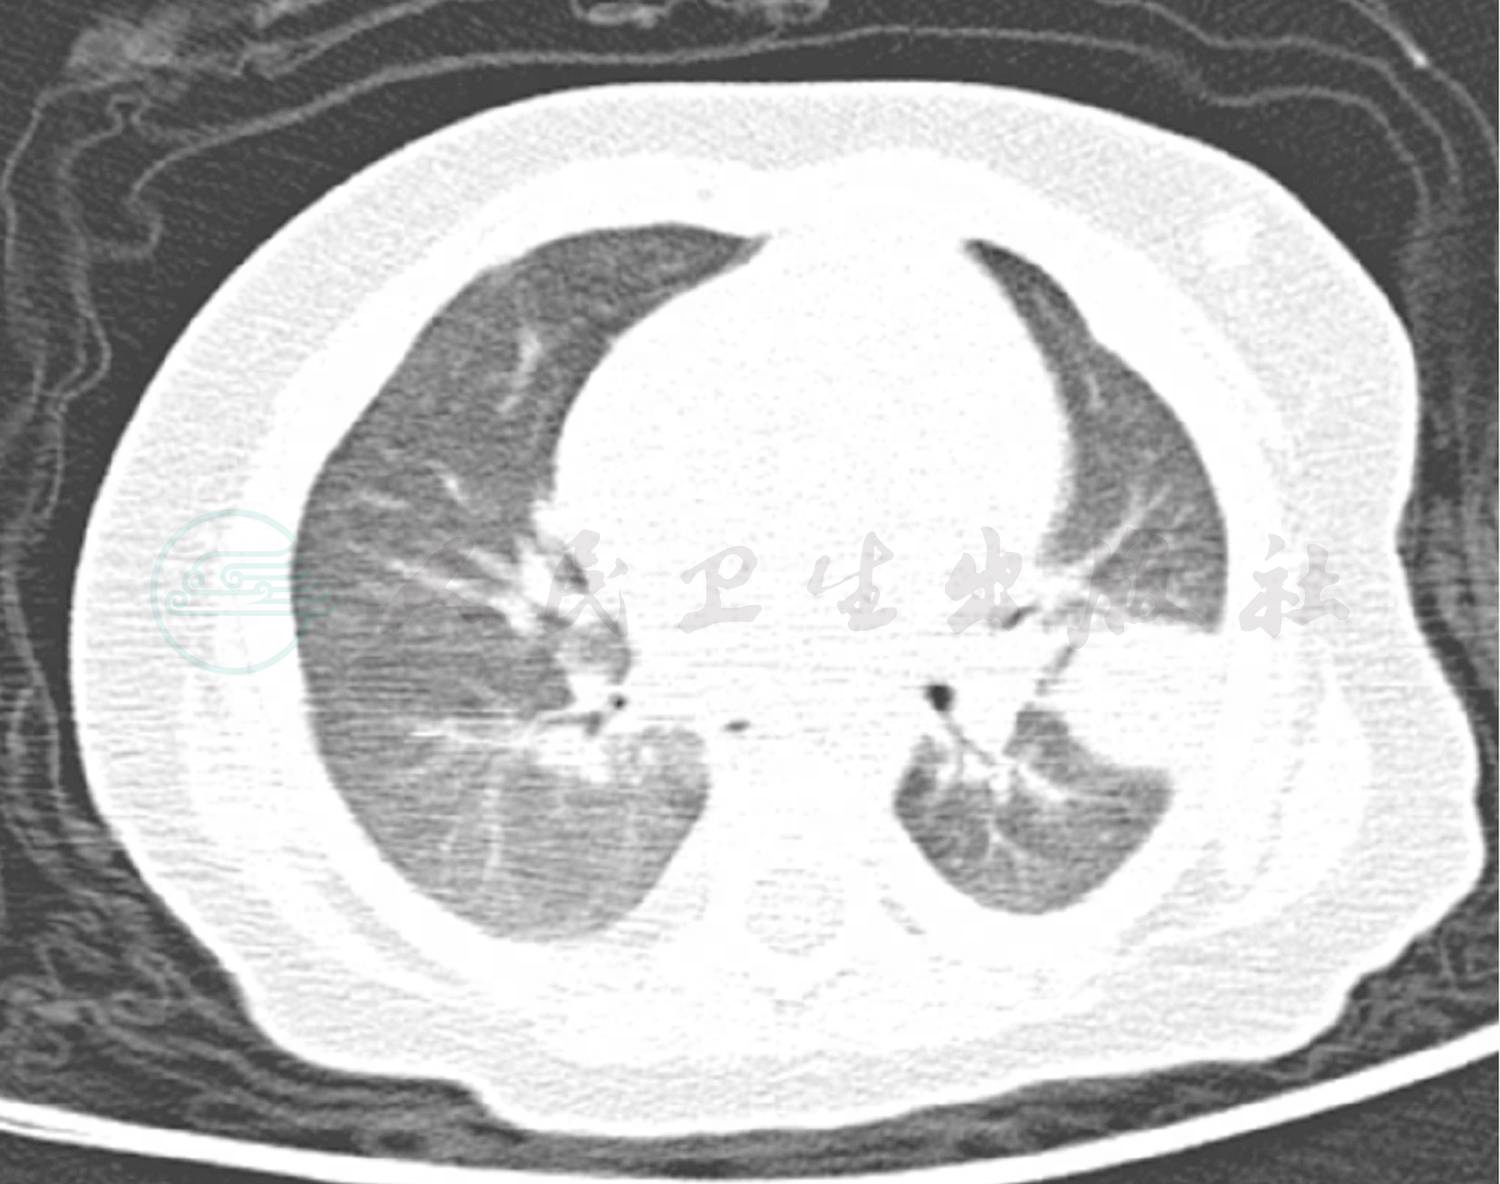

现病史:患儿13天前无明显诱因出现发热,体温最高达39.0℃,口服美林后热可退,4~6小时后复升,无寒战、抽搐,伴咳嗽,为阵咳,有痰咳不出,咳嗽剧烈时喉部可闻及“咝咝”声,无呼吸困难,无低热、盗汗,无明显消瘦。于当地医院胸片检查(图1)提示“双肺纹理增粗、模糊”,诊断“肺炎”,予“头孢、红霉素”静脉滴注共8天,静脉滴注4天后体温平稳,仍有咳嗽,复查胸片(图2)提示肺炎加重。来笔者医院就诊,门诊肺CT(图3)提示左肺上叶占位性病变,遂于小儿外科住院治疗,胸腔彩超提示左侧胸腔液性暗区,内可见点片状回声;诊断“肺炎,肺结核不除外,肺内占位性病变不除外”予二代头孢抗炎及化痰治疗。请胸科医院会诊考虑“左肺上叶炎症性病变可能性大,不除外‘占位性病变’或‘结核’可能;建议完善磁共振及增强CT检查”。2天前于外院就诊,考虑“细菌或真菌感染,不除外结核及先天性肿瘤”未接受治疗返回。2天前患儿再次发热,体温波动于38~39℃,仍咳嗽,至笔者科室进一步诊治。

辅助检查:门诊血常规:WBC 12.1×109/L,NE 70%;RBC 3.9×1012/L,HGB 110g/L;PLT 206×109/L。门诊肺 CT(图3):双肺纹理增粗模糊,左肺上叶占位性病变。胸腔彩超:左侧胸腔腋后线第2、3肋间可见2.4cm×2.7cm液性暗区,内可见点片状回声。

图3 笔者医院门诊肺CT结果